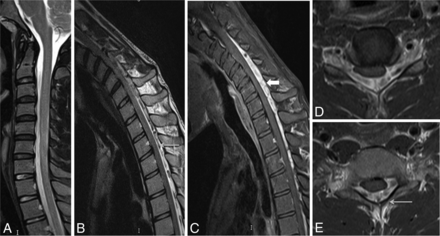

A 22-year-old man with wasting and weakness of the right hand and forearm muscles with cold paresis. Neutral position sagittal T2-weighted MR image (A) shows a normal appearance of the cervical cord. Flexion MR T2-weighted image (B) shows an enlarged posterior epidural space with multiple flow voids (arrow). Postgadolinium fat-suppressed sagittal T1-weighted flexion MR image (C) shows an enhancing epidural venous plexus extending from the C3 to T3 vertebral levels (block arrow). Axial postgadolinium T1 fat-suppressed images (D and E) show the enhancing posterior epidural venous plexus with flow voids within (arrow) and asymmetric flattening of the right hemicord.